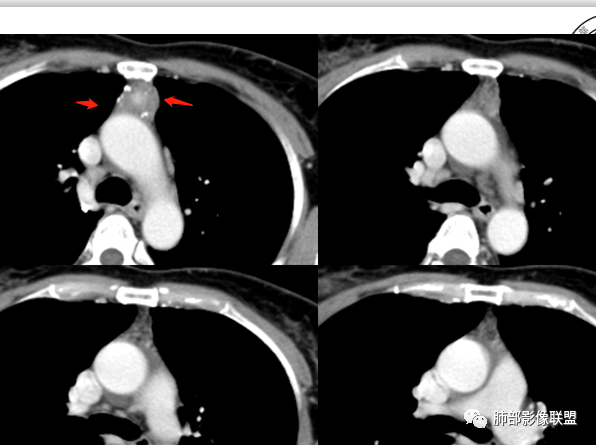

红星:女性病人48岁,前上纵隔,类圆形的实性病变,平扫密度比较均匀,周围卷见点状的钙化灶,增强扫描明显的强化, 多时相扫描中心可见跟大血管强化幅度一致的结节灶。常规胸腺瘤?鉴别血管瘤?

春秋:48岁,女性,前纵膈软组织肿物,有分叶,边缘毛糙,周边多发点状钙化,强化可见明显强化区,考虑血管瘤,鉴别胸腺癌。

周太狼:中年女性,前纵隔肿块,边界清,内不规则钙化灶,增强中央明显强化,与邻近血管强化程度相似。纵隔内无明显增大淋巴结。考虑良性或低度恶性病变。疾病谱:CD、副节、血管瘤、胸腺瘤/癌。个人倾向于CD或血管瘤可能大一些。

三个石头:前纵隔占位,残余胸腺组织可见,边缘钙化,增强中央出现与血管同步强化结节,病灶延迟强化。脉管瘤?胸腺瘤?血管瘤?异位甲状腺?

不吝慷慨:前上纵隔,边缘钙化,中央强化非常明显,形态不考虑胸内甲状腺,胸腺瘤强化又太明显,考虑嗜铬肿瘤或脉管类肿瘤。

黄兴:48岁,女性,前纵膈软组织肿物,有分叶,边缘毛糙,周边多发点状钙化,强化可见明显强化区,首先考虑胸腺瘤,鉴别血管瘤和内胚窦癌(需要生化)。

滴水海:疾病谱上面老师都说全了,CD,副节瘤,胸腺瘤,脉管瘤,异位甲状腺,畸胎瘤。副节瘤好像不会发生在此位置,胸腺瘤如此钙化一般A型,但周围脂肪间隙模糊,也可见增粗血管,不太像,异位甲状腺及畸胎瘤都无此征象,可能性较小。剩下巨淋和脉管瘤,巨淋边缘钙化不多见。脉管瘤见的少,按理可以有此表现。脉管瘤>巨淋>胸腺瘤>异位甲状腺

冥冥之中:48岁,排除生殖,形态及强化,排除淋巴瘤。胸腺来源瘤或者癌,包膜钙化支持瘤,但是强化后周围脂肪间隙模糊,与主动脉壁分界不清,提示侵袭性,考虑胸腺瘤AB或者B2以下病灶内累圆形高强化结节,提示血管破坏,有出血。综合考虑胸腺瘤B2-3,待排胸腺癌。

南边:定位前纵隔没问题

边缘多发条状、线样、结节状钙化

南边:边界尚清,位于残留胸腺组织内

中央结节状强化, 类似于血管强化

定性:偏良性病变,血管瘤?胸腺瘤?